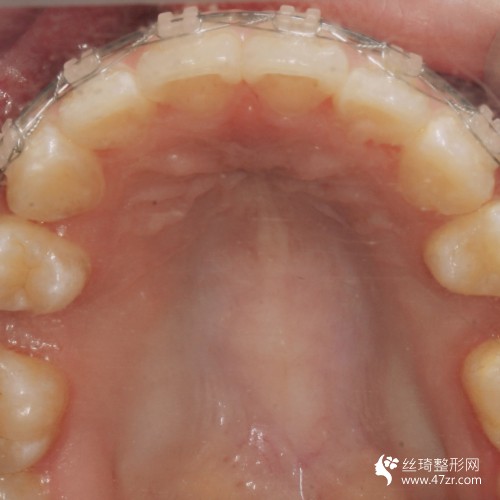

3.手術案例介紹

術前:因為我的牙齒很不好看,所以這種情況給我的外在形象帶來了很大的影響,為了改變我決定到醫(yī)院去做手術,醫(yī)師根據我的情況給我做了牙齒矯正手術的方案,看到手術方案之后,我就決定在昆明美奧口腔醫(yī)院做手術,因為這所醫(yī)院很正規(guī),而且醫(yī)生也是很專業(yè)的,所以我覺得完成手術之后的果會很不錯。

術中:在進行手術過程中是比較沒問題沒多少痛感的,因為醫(yī)生的手法很輕柔,所以我覺得手術過程還是比較理想的,醫(yī)生說手術恢復起來會比較慢,讓我聽他的話好好的進行護理。

術后7天:這幾天一直在聽醫(yī)生的話進行很好的護理,沒有吃堅硬的東西,也沒有吃一些太油膩的食物,所以手術的恢復還算不錯吧,但是這才是剛開始醫(yī)生說要慢慢的去恢復,不要心急,所以我也就只能慢慢的等待了。

術后90天:很多朋友都說我現在的恢復是比較不錯的,因為整體看上去更加好看了,我也覺得是這樣的,雖然手術還沒有得到完全的恢復,但是可以看出來有了很好的改良。

術后160天:手術結束之后不但使我的牙齒得到了很好的矯正,而且我整個人的形象也變得更美觀了,所以我對手術是感到很滿意的,真的很感謝醫(yī)生,現在手術的恢復還沒有完全的恢復好,所以還是需要進行很好的護理。

術后365天:手術恢復的差不多了,今天到醫(yī)院去復診的時候,醫(yī)生說恢復的很好,在整個手術過程中都沒有出現任何不良的情況,真的是太滿意了,很感謝曾強醫(yī)生。